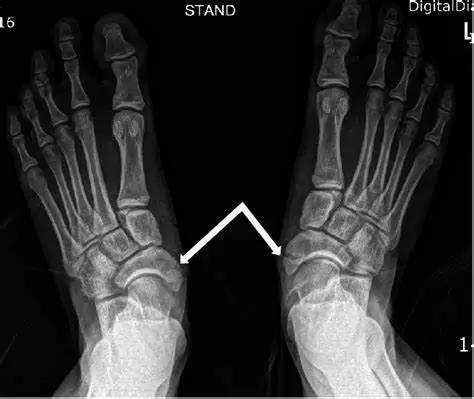

到了医院,检查了小李的足踝,告诉她:踝关节内外侧的韧带都没太大问题,怀疑有“副舟骨综合征”,也是叫“症状性副舟骨”,并是不普遍说法的“崴脚”,去拍了X线片。报告上写着:副舟骨形成····这···到底是个什么病???

X线平片显示舟骨内后方有小骨块,部分能够见到小骨块明显分离。

II型被称为假关节型,副舟骨与舟骨以纤维软骨相连,被称为“两分舟骨”,可引发疼痛;